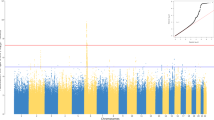

Observed genotypes were used to estimate allele frequencies for each SNP and departures from Hardy–Weinberg equilibrium (HWE) were assessed using either a Pearson goodness-of-fit test or, for SNPs with a MAF <5%, a Fisher exact test (Weir 1996). Estimates of pair-wise linkage LD based on the r 2 squared statistic were obtained using Haploview software, version 3.32 (Barrett et al. 2005).

SNP associations with immune response outcomes were individually evaluated using linear regression models. Simple linear regression was used for MV antibody levels, which had only one measured value per individual. Repeated measures approaches were implemented for the cytokine secretion and Elispot variables, simultaneously modeling the multiple observed measurements. This was achieved by including the genotype variable in the regression model, together with a variable representing stimulation status, and testing the statistical significance of the corresponding genotype-by-stimulation status interaction term. In these models, we allowed for within-subject correlations without imposing any constraints on their structure within a person. Primary tests of association assumed an ordinal (log-additive) SNP effect.

All association analyses adjusted for age at enrollment, race, gender, age at first measles vaccination, age at second measles vaccination, and cohort status (cohort 1 vs. cohort 2) to account for their potential impact on the measured immune responses. Data transformations were used to correct for data skewness in all linear regression models. An inverse normal transformation was used for all cytokine secretion and Elispot outcome variables, and a log transformation was used for the antibody response measure. All statistical tests were two-sided and, unless otherwise indicated, all analyses were carried out using the SAS software system (SAS Institute, Inc., Cary, NC).

Associations between SNPs in TLR with associated intracellular signaling molecules and antibody response

Genotyping data were analyzed for the combined cohort of subjects (n = 745) and separately for Caucasians (n = 598). We also performed a secondary analysis of data collected for the African-American subgroup (n = 89). Overall, 16 SNPs were significantly associated (p < 0.01) with variations in MV-induced neutralizing antibodies. Six of these SNPs were positioned in the coding and regulatory regions of the TLR2, TLR4, MAP3K7 (TAK1), and TRAF6 genes (Table 1). In the combined cohort of subjects major allele variants AA of two coding synonymous SNPs (rs5030710 and rs3804100) of the TLR4 and TLR2 genes were associated with an allele dose-related decrease (2,209 vs. 830 mIU/ml, p = 0.001) and an allele dose-related increase (660 vs. 892 mIU/ml, p = 0.002) in measles-specific antibody response, respectively. We found significant associations between two promoter SNPs (rs711264, 970 vs. 613 mIU/ml, p = 0.001 and rs806287, 919 vs. 612 mIU/ml, p = 0.005; r 2 = 0.99) located in the MAP3K7 gene on chromosome 6q16.1 and dose-related decreases in measles antibodies. As expected, in the Caucasian and African-American subgroups we found associations for the promoter and coding SNPs in the MAP3K7 and TLR4 genes (rs711264 and rs5030710), respectively. Specifically, increased carriage of minor allele A for rs711264 located in the promoter region of the MAP3K7 gene, was associated with a dose-related decrease in antibodies (974 vs. 612 mIU/ml, p = 0.006) in the Caucasian subgroup. Major allele variant A for a coding SNP (rs5030710; 624 vs. 1,729 mIU/ml, p = 0.009) in the TLR4 gene was associated with an allele dose-related increase in antibodies in the African-American subgroup.